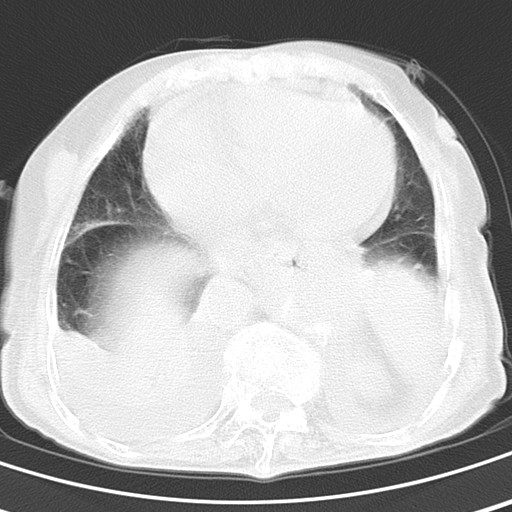

女,93岁,摔伤后检查。

右肺炎症,心功能不全伴双侧胸腔积液,右下肺膨胀不全,食管裂孔疝,冠脉钙化,心包少量积液,左侧肋骨骨折,请上传骨窗.

右侧锁骨\\肩胛骨骨折、右侧湿肺,心功能不全伴双侧胸腔积液,右下肺膨胀不全,左膈破裂或食管裂孔疝,冠脉钙化,心包少量积液,请上传骨窗.

右肺炎症,心功能不全伴双侧胸腔积液,右下肺膨胀不全,食管裂孔疝,冠脉钙化,心包少量积液,左侧肋骨骨折,右肩甲骨粉碎性骨折。93岁,高寿哇!

右肺炎症,心功能不全伴双侧胸腔积液,右下肺膨胀不全,食管裂孔疝,冠脉钙化,心包少量积液,左侧肋骨骨折,右肩甲骨粉碎性骨折。